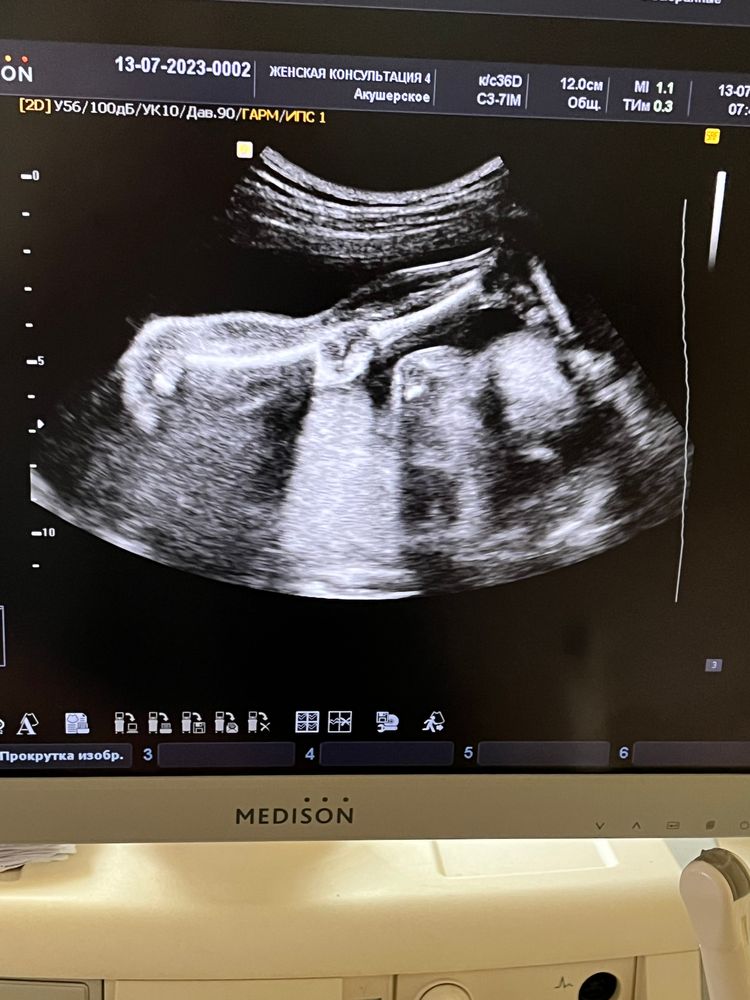

22 недели видео

22 недели видео 114 фото